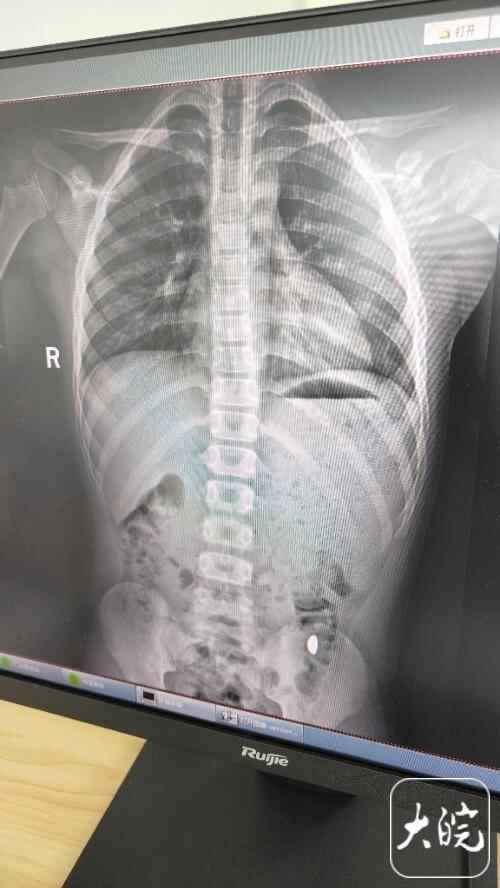

昆山市第五人民医院门诊病历单显示,医生在现病史一栏写着,患儿5天前误吞约10克黄金,期间解2次大便未发现,目前无腹痛、呕吐等症状,诊断结果显示胃内有异物。

周小刚告诉记者,普外科曾接诊不少儿童吞食异物的情况,但很难直接给出结论,需要结合具体的情况进行判断,两者对应不同的情况,各有优势。一些小型异物可能更容易自行排出,但若异物较大或较重,甚至异物本身有对身体存在危害的特性,或是异物长时间滞留,还是需要考虑内镜治疗或者外科手术取出。

他提醒各位家长,在各类异物中,有几类情况尤其需要注意,最好尽快就医:若异物直径大于2.5厘米,如硬币、石头、玉牌等,或异物长度大于6厘米的条形物品,这些异物患儿较难自行排出,异物更容易停留于消化道;若异物本身对人体存在危害,如带电、具有腐蚀性的纽扣电池,或具有磁力的磁力珠等,这类异物可能直接对患儿身体造成危害。